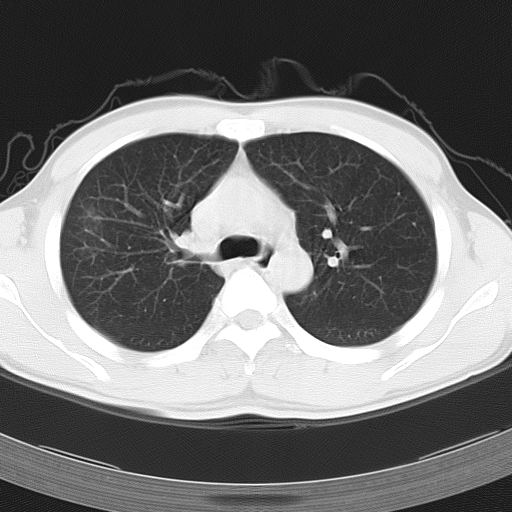

男,34岁,咳嗽2~3个月,无咳血,病初有发热。

两上肺磨玻璃样改变,均位于肺外周,考虑1、肺泡蛋白沉着症?2、肺泡炎?请询问有无养鸟史 3、脱屑性间质性肺炎?建议进一步检查、复查随访

两上肺的ggo,靠近胸膜,不是以节段分布,青年男性,个人意见为吸入性的真菌感染可能为大------------呼吸内科医生

两肺上叶近胸膜磨玻璃样阴影,考虑1、炎性病变。 。2、过敏性炎症?

病灶特点:

分布在肺野的外带,病灶边缘清楚,病灶以磨玻璃影为主夹杂少许纤维状高密度影

支持zhangzhongshou主任,考虑蛋白沉着症可能性大

(1)斑片状磨玻璃影:指肺野密度朦胧增加,内可见肺血管纹理影,系肺泡腔内充满低密度的磷脂蛋白物质所致。

(2)其内部小叶间隔或小叶内间隔增厚所形成的网格状影,为小叶间隔水肿、肺泡壁内淋巴细胞和巨噬细胞浸润以及小叶内淋巴管扩张的缘故。

(3)病灶边缘清楚,呈地图样分布于肺野外围或肺门及中央区。

病变分布以双上肺叶外带明显,双下肺未见异常,此一点不十分支持肺泡蛋白质沉着症,病变未见铺碎路石征,也不肺泡蛋白质沉着症。考虑间质性肺炎,结核不除外。

肺泡蛋白沉积症;胸膜下区磨玻璃样,实变区见纹理走形,地图样改变。做mri。

文献报告:x线表现 (1)中央型:肺内弥漫细小模糊结节或羽毛状浸润阴影。其内可见空气支气管征,病变自两肺门向外围延伸分布,形成蝶翼状外貌,甚似肺泡性肺水肿,为本病典型表现。(2)外围型:小叶浸润病变分布于两肺外围或一侧外围,轮廓模糊。

ct表现 (1)中央型:表现为蝶翼状浸润性阴影对称分布于两侧肺门周围,其内可见支气管充气征,病变区与正常肺组织分界清楚。(2)外围型:表现为多发性条片状、斑片状及斑块状高密度影,弥散、对称或不对称分布于两肺或一侧肺外围部位。病变区与正常肺组织及脏层胸膜面分界清晰,呈地图样改变。hrct可显示小叶间隔增厚及肺小叶内淡淡的密度增高影等细微结构,同时易发现肺大疱、肺气囊及节段性肺不张。

再仔细阅读该病人的ct片,我们不难发现,病例所表现的正是外围型的肺泡蛋白沉积症表现,即:为多发性条片状、斑片状及斑块状高密度影,弥散、对称或不对称分布于两肺或一侧肺外围部位。病变区与正常肺组织及脏层胸膜面分界清晰,呈地图样改变。